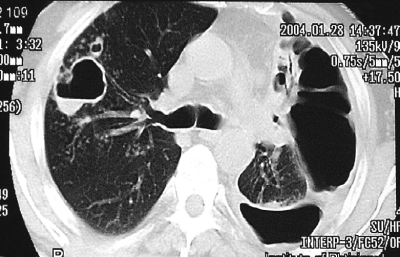

Для подострого диссеминированного туберкулёза лёгких, развивающегося при гематогенном рассеивании микобактерий, характерна субтотальная очаговая диссеминация с преимущественной локализацией очаговых теней в верхних и средних отделах лёгких. Очаговые тени в основном крупные (5-10 мм), малой или средней интенсивности (субтотальная крупная равноочаговая диссеминация), обычно с нечёткими контурами (рис. 18-27). Некоторые очаговые тени сливаются и образуют фокусные затемнения с участками просветления, обусловленными распадом лёгочной ткани. Иногда деструктивные изменения представлены тонкостенными кольцевидными тенями.

Рис. 18-27. Подострый диссеминированный туберкулёз. а - фрагмент обзорной прямой рентгенограммы; б - КТ.